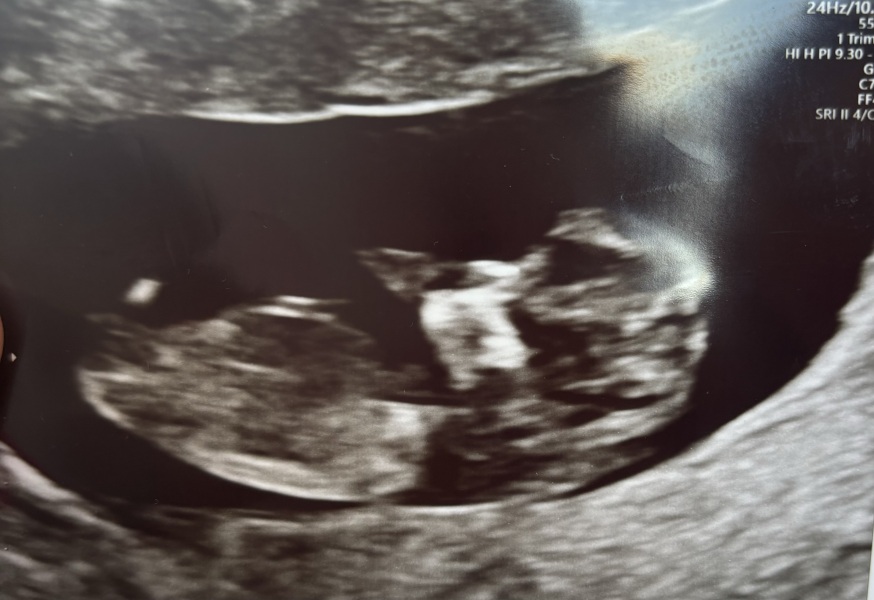

11 weeks today what does everyone think 💙💖

Baby gender